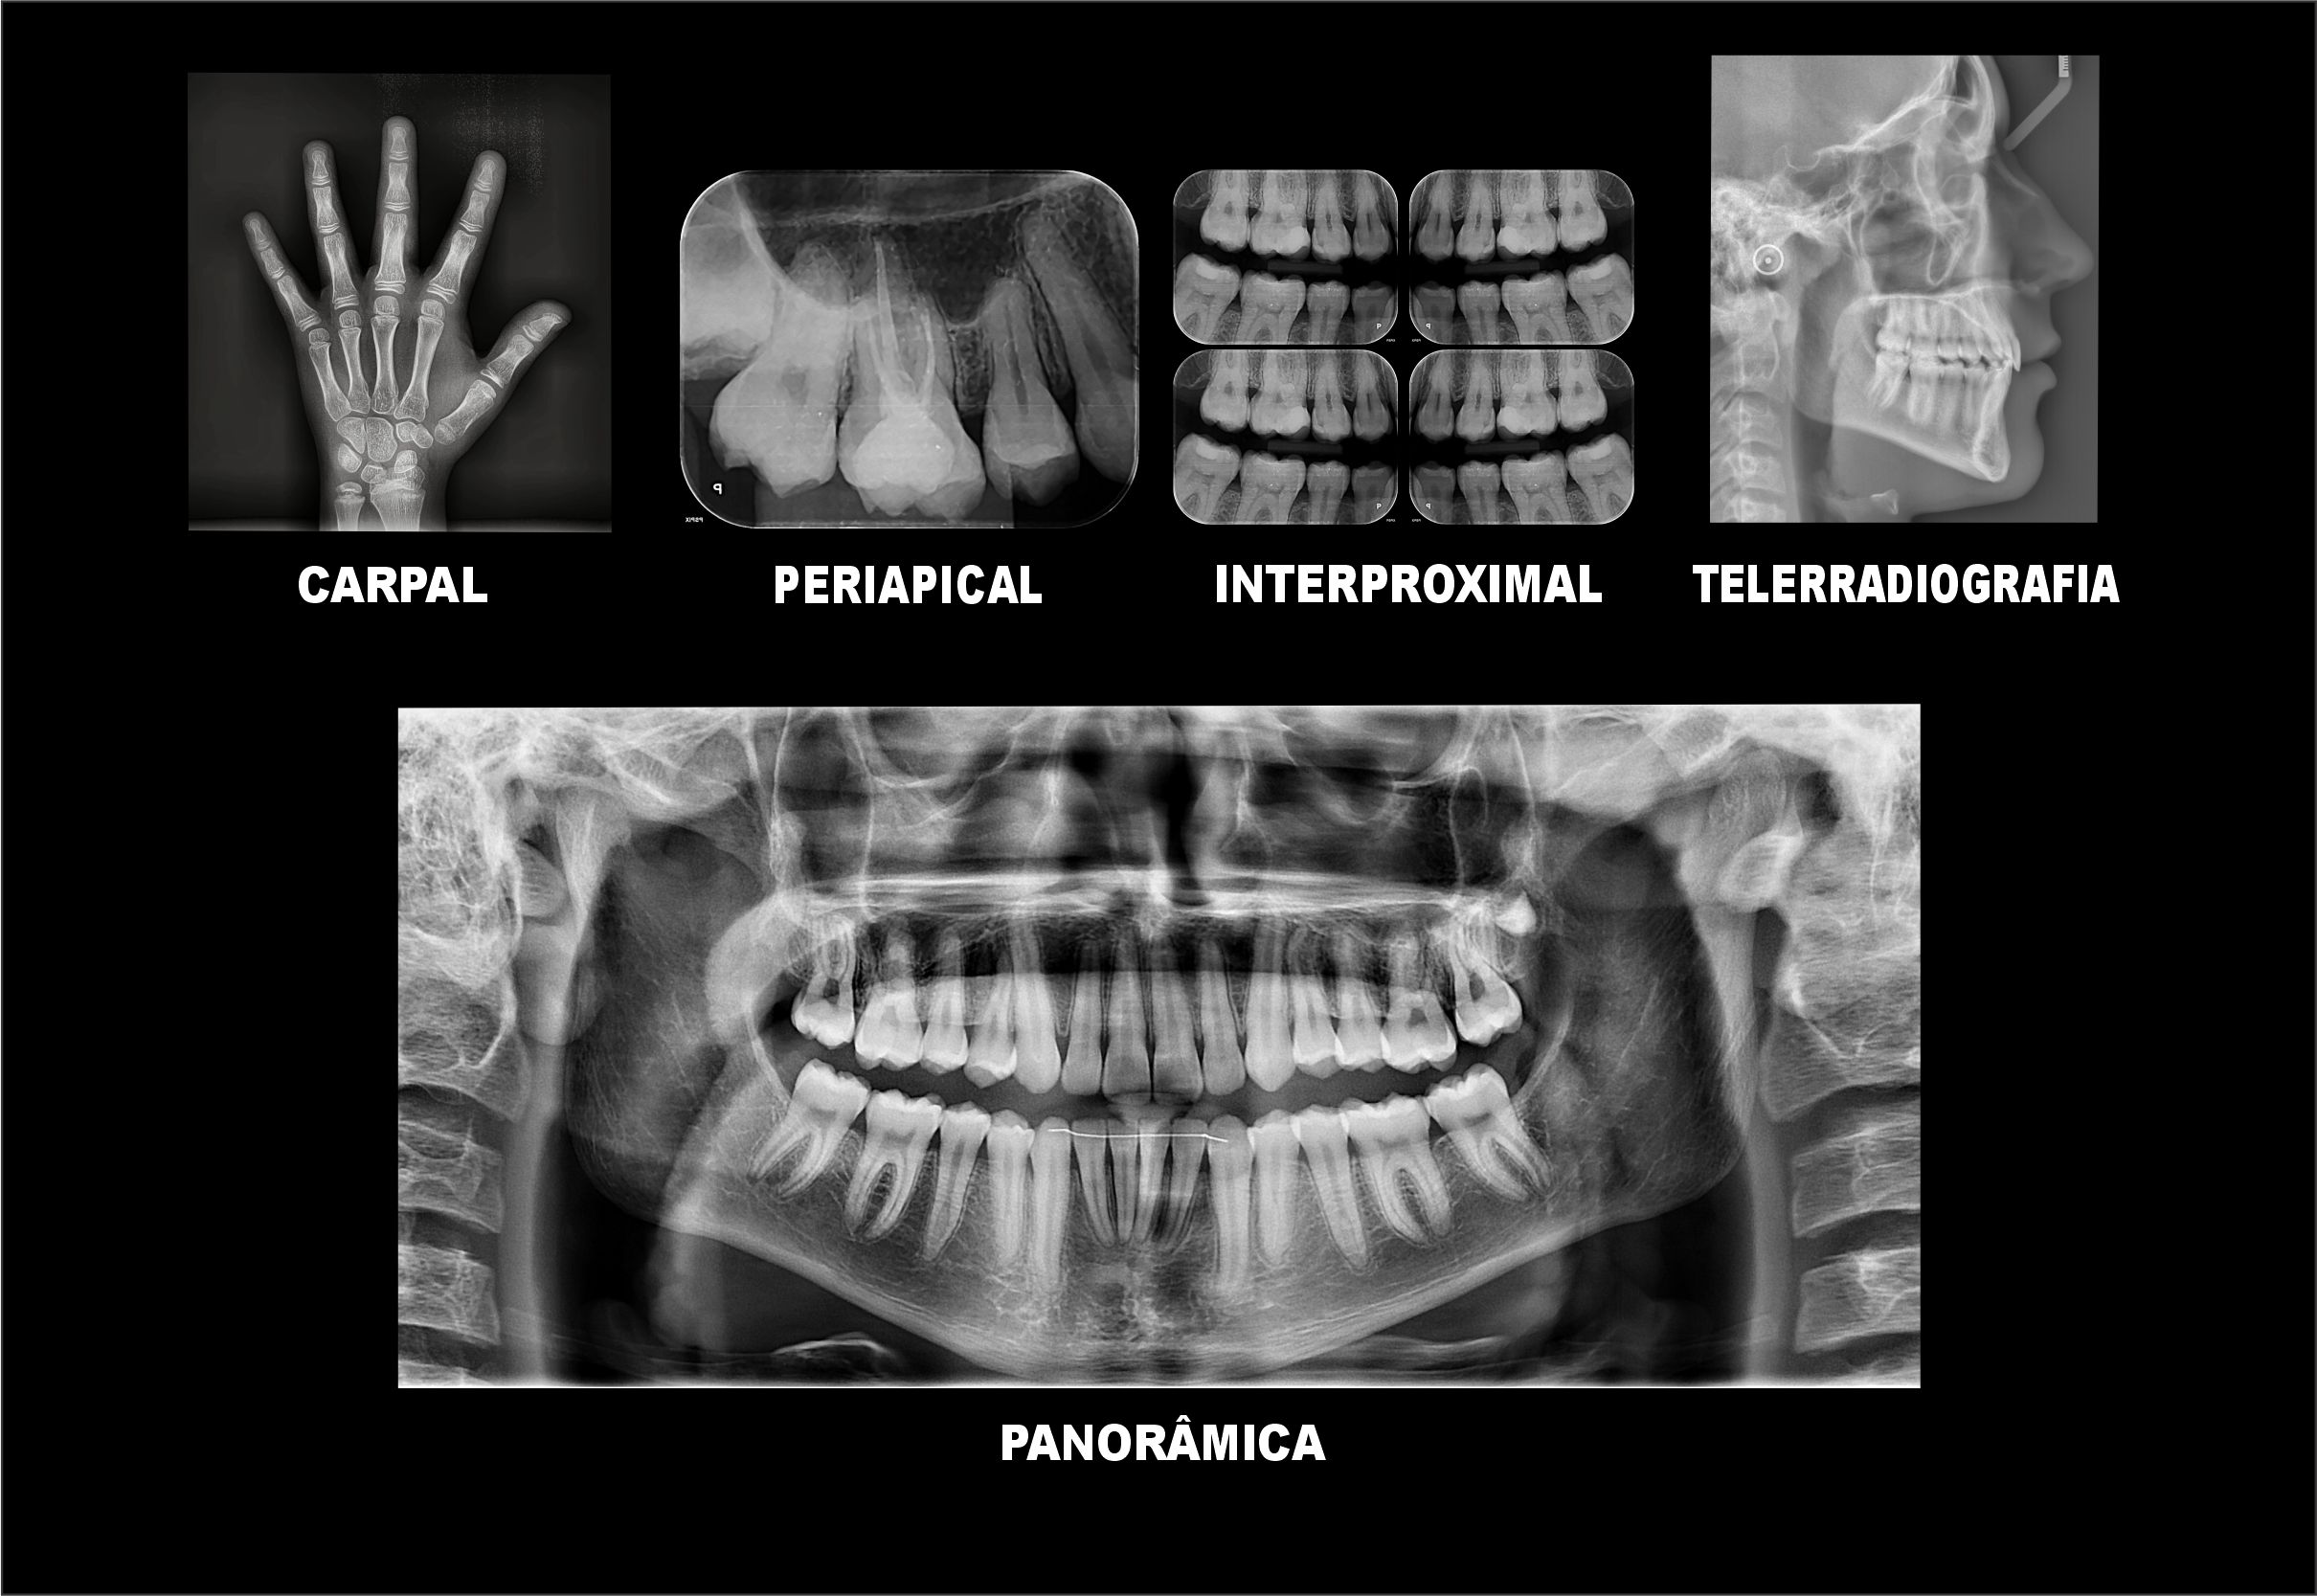

Radiografias Digitais

- Raio X Panorâmico

- Telerradiografia

- Periapicais

- Interproximais

- Radiografia de Mão e Punho (Idade Óssea)